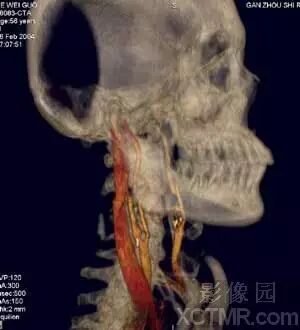

2)血管系统

VR作为MS-CTA的主要后处理技术在血管系统特别是对动脉血管系统病变要以清晰、确切地显示大范围复杂血管的完整形态、走行和病变,图像立体感强,能以多角度直观地显示病变与血管、血管之间以及血管与周围其它器官之间的三维空间解剖关系,其诊断价值已经被临床医生认可。对大动脉血管病变如:动脉瘤、动静脉畸形、狭窄、梗塞、闭塞、夹层和血管壁的钙化等的诊断已经基本取代了DSA检查。对脑动脉瘤的诊断国、内外有关研究报告证实3D-CTA具有很高的准确性、敏感性和特异性,可以确切地检出瘤体直径<3mm的脑动脉瘤。作为一种快速和非创伤性检查手段,可以准确地显示瘤体的位置、形态和大小,评价瘤颈部与瘤体、载瘤动脉和周围血管之间的空间关系,模拟手术入路为选择适当的手术治疗方案提供直观、可靠的依据,可以作为脑动脉瘤的首选影像学诊断方法。近年来,有许多文献报道主张用3D-CTA取代或部分取代DSA诊断脑动脉瘤。